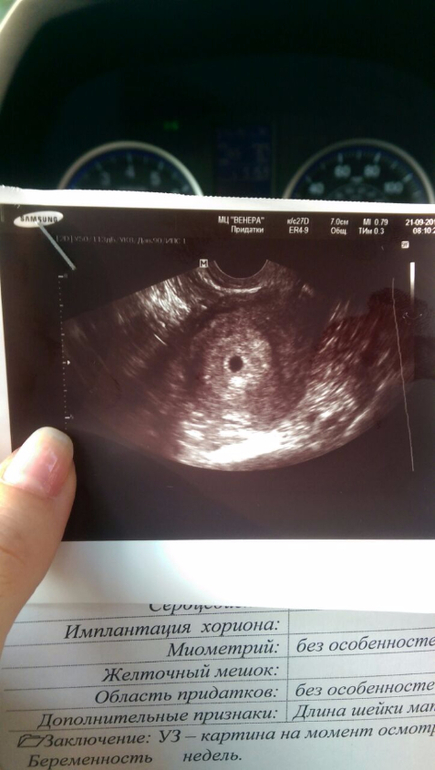

Беременность- 1 триместр ( только до 10 недель)Я тут пересматриваю узи своё и вот что мне интересно. Я сейчас скину 3 фотки. Оригинал и 2 с обведёнными кругами. Я присмотрелась и такое чувство, будто бы там как перегородка что-ли. Ну в общем посмотрите. Вот плодное яйцо более темное и сбоку как что-то круглое, но не такое тёмное. Что это?))

У вас чёткий круг. А я на своём возле чёткого круга вижу ещё как один круг, только не такой тёмный